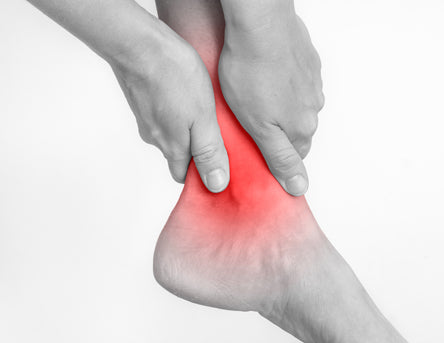

Arthritis is a painful inflammation of the joints which can cause discomfort and stiffness in the foot or ankle.

There are different types of arthritis which commonly affect the foot or ankle, including osteoarthritis, rheumatoid arthritis and gout. Arthritic pain can range from mild to severe. Each type of arthritis can cause different symptoms, but in all of them inflammation is a factor. Osteoarthritis is a common type of joint disease, also called degenerative joint disease or “wear and tear” arthritis in which cartilage between joints breaks down leading to swelling, stiffness, and pain. Rheumatoid arthritis is an autoimmune disease which causes painful swelling in the joint lining and eventually causes joint erosion and bone deformity.

Gout is a very common form of arthritis which differs from the other types and is usually noticed with the sudden onset of pain in the joint of the big toe.